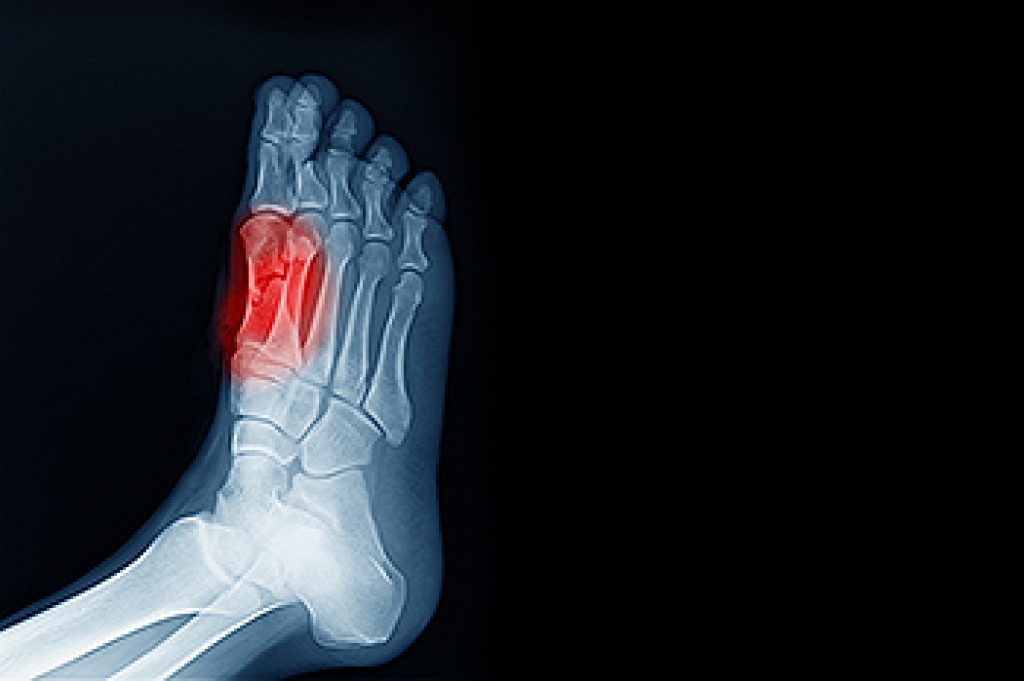

Ingrown toenails are caused when the corner or side of a toenail grows into the soft flesh surrounding it. They often result in redness, swelling, pain, and in some cases, infection. This condition typically affects the big toe and may recur if it is not treated properly.

Some symptoms of ingrown toenails are redness, swelling, and pain. In rare cases, there may be a yellowish drainage coming from the nail.